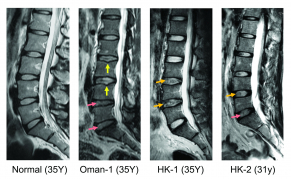

正常椎間盤中央部分有凝膠狀的分子,發揮其緩衝作用,CHST3就是使凝膠分子保持水分,是人體中不可缺少的。它同時使脊柱具有運動功能,並在日常活動中吸收衝擊力。由於基因差異使合成的CHST3之數量產生變化,促使椎間盤中央部分失去水分,從而令椎間盤出現退化。